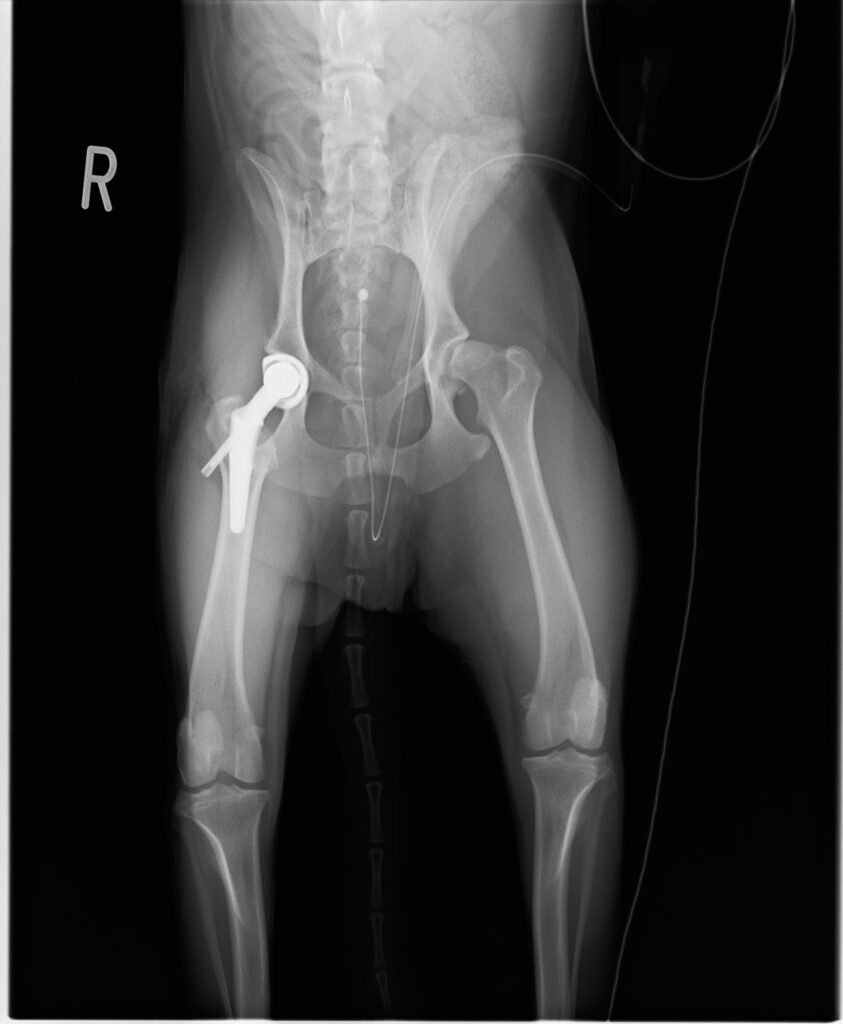

- 実施術式:人工股関節全置換術(THR)

THRは、変形した大腿骨頭と寛骨臼側を、金属とインプラントに置換し、疼痛の軽減と関節機能の再建を目指す術式です。一般的な流れは、股関節へアプローチし大腿骨頭を切除したうえで大腿骨内にステムを設置し、寛骨臼側にカップを固定して関節を再構成します。術中は可動域と安定性、脚長差の過大がないかを確認して閉創します。 期待できる点として、疼痛の大幅な軽減と歩様改善が見込まれ、日常生活動作の回復に寄与します。一方で、人工股関節の脱臼、感染、インプラントのゆるみ・破損、周囲骨折などの合併症リスクが残るため、術前に十分な説明と適応判断が必要です。

術後は入院下で疼痛管理と創部管理を行い、画像評価でインプラント位置と整復状態に大きな問題がないことを確認して退院判断としました。退院後は運動再開を段階化し、再診時に歩様と画像所見を踏まえて制限内容を調整します。